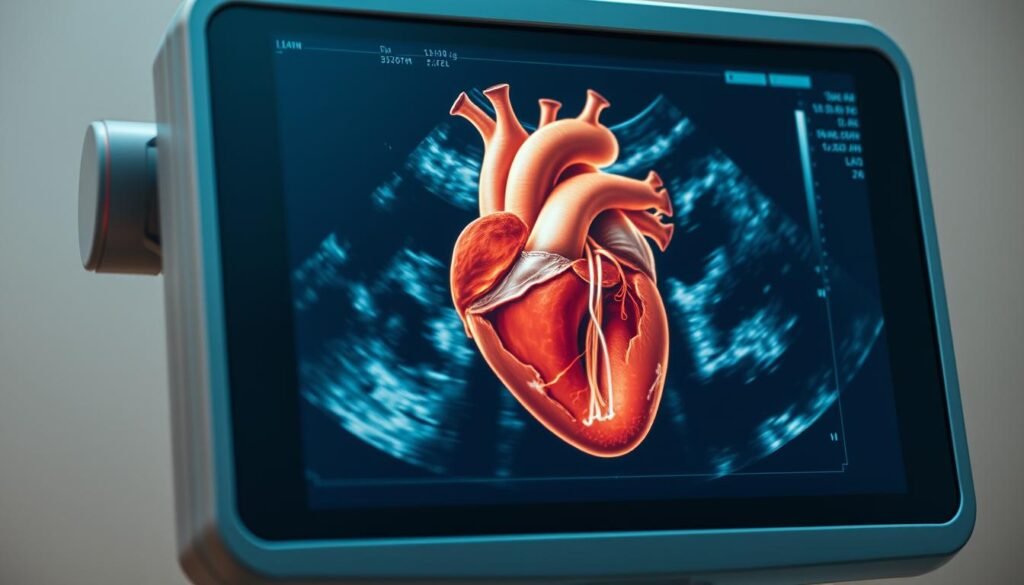

L’Échographie Cardiaque : Diagnostic et Procédure Médicale

Guide complet sur l’échographie cardiaque : comprendre la procédure et les résultats pour un diagnostic cardiaque précis.